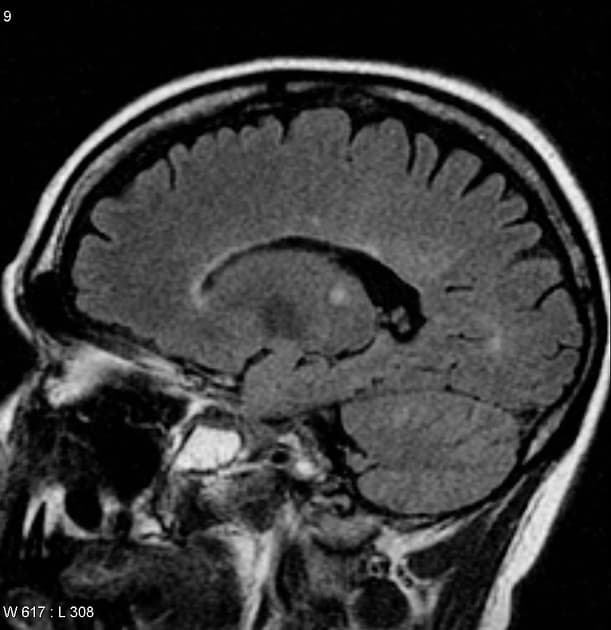

- Ghi nhận nhiều tổn thương kích thước thay đổi, ở hai bên tại vùng quanh não thất (periventricular), vùng cận vỏ (juxtacortical), vùng tiểu não, chi sau bên trái của bao trong (left posterior limb of the internal capsule) và cánh cầu bên trái (left brachium pontis).

- Các tổn thương vùng quanh não thất định hướng vuông góc với não thất (Dawson fingers).

- Các tổn thương biểu hiện tín hiệu giảm trên T1, tăng tín hiệu trên T2 và FLAIR.

- Một số tổn thương cho thấy hiện tượng T2 shine-through (tín hiệu tăng trên DWI và ADC tăng), trong khi một số khác, chủ yếu là các tổn thương quanh não thất, biểu hiện tín hiệu sáng dạng viền trên DWI với ADC ngoại vi giảm (hạn chế khuếch tán thật sự – true restriction).

- SWI phát hiện dấu hiệu tĩnh mạch trung tâm (central vein sign) tại tổn thương ở chi sau của bao trong (PLIC).